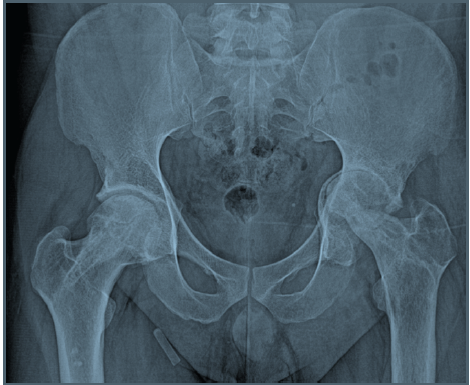

He continued to have mild pain in the left hip, which gradually progressed over the next 5 years. He did not have any reactivation of infection for 5 years. He was on tacrolimus for his nephropathy, the dose being adjusted as per his disease activity until he attained remission. By 2025, he was unable to bear weight and walk and also noticed progressive shortening of the left lower limb. He had a flexion deformity of 20°. All other movements were limited to 20° range but were intact. His X-ray showed destruction of the femoral head with Grade 2 Protrusio acetabulii (Fig. 2).

Figure 2: Left hip protrusio acetabuli Grade 2 with joint space narrowing, femoral head destruction, and arthritis.